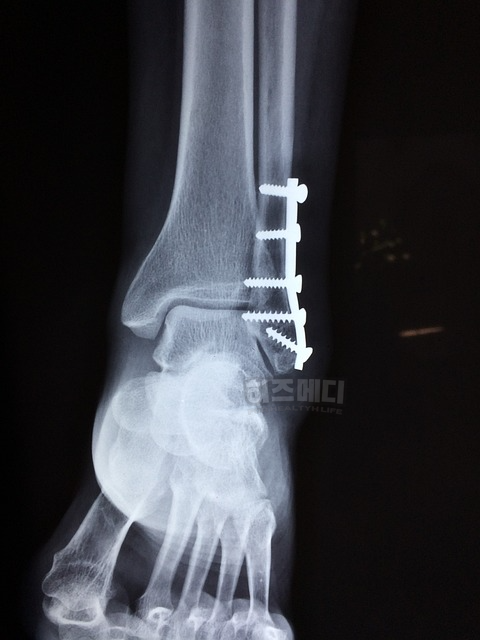

요추 중에서는 이전에 골절이나 수술을 받은 뼈가 있으면 제외하기도 합니다. 또한 퇴행성 변화가 너무 심한 경우에도 제외합니다.

고관절의 대퇴골을 검사할 때도, 만약 고관절에 인공관절이 있거나 골절 등의 손상 이력이 있다면 제외합니다. 인공관절이나 비정상적인 뼈는 실제 뼈 밀도를 정확히 반영하지 않기 때문에 검사에 포함하지 않는 것이 원칙입니다.